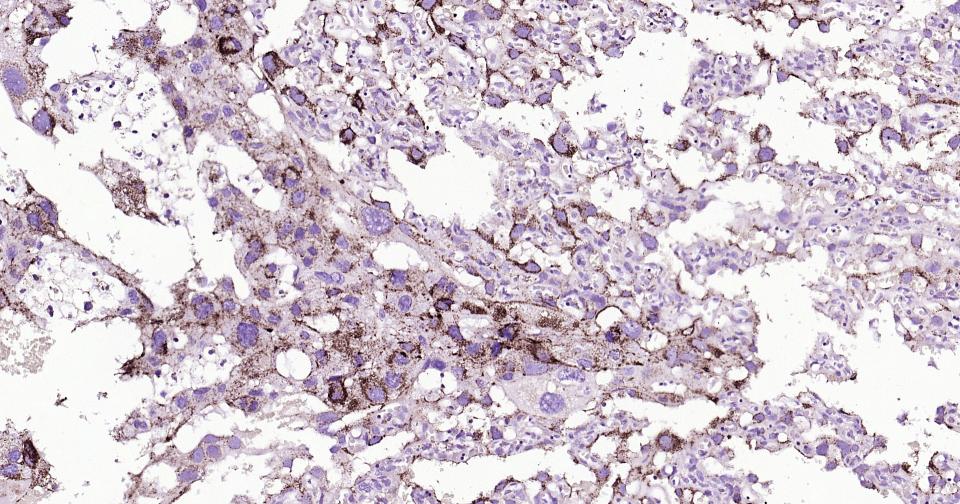

Paraformaldehyde-fixed, paraffin embedded Human thyroid cancer;Antigen retrieval by boiling in sodium citrate buffer (pH6.0) for 15 min; Antibody incubation with LAMP2 Monoclonal Antibody, Unconjugated (bsm-61207R) at 1:200 overnight at 4°C, followed by conjugation to the bs-0295G-HRP and DAB (C-0010) staining.